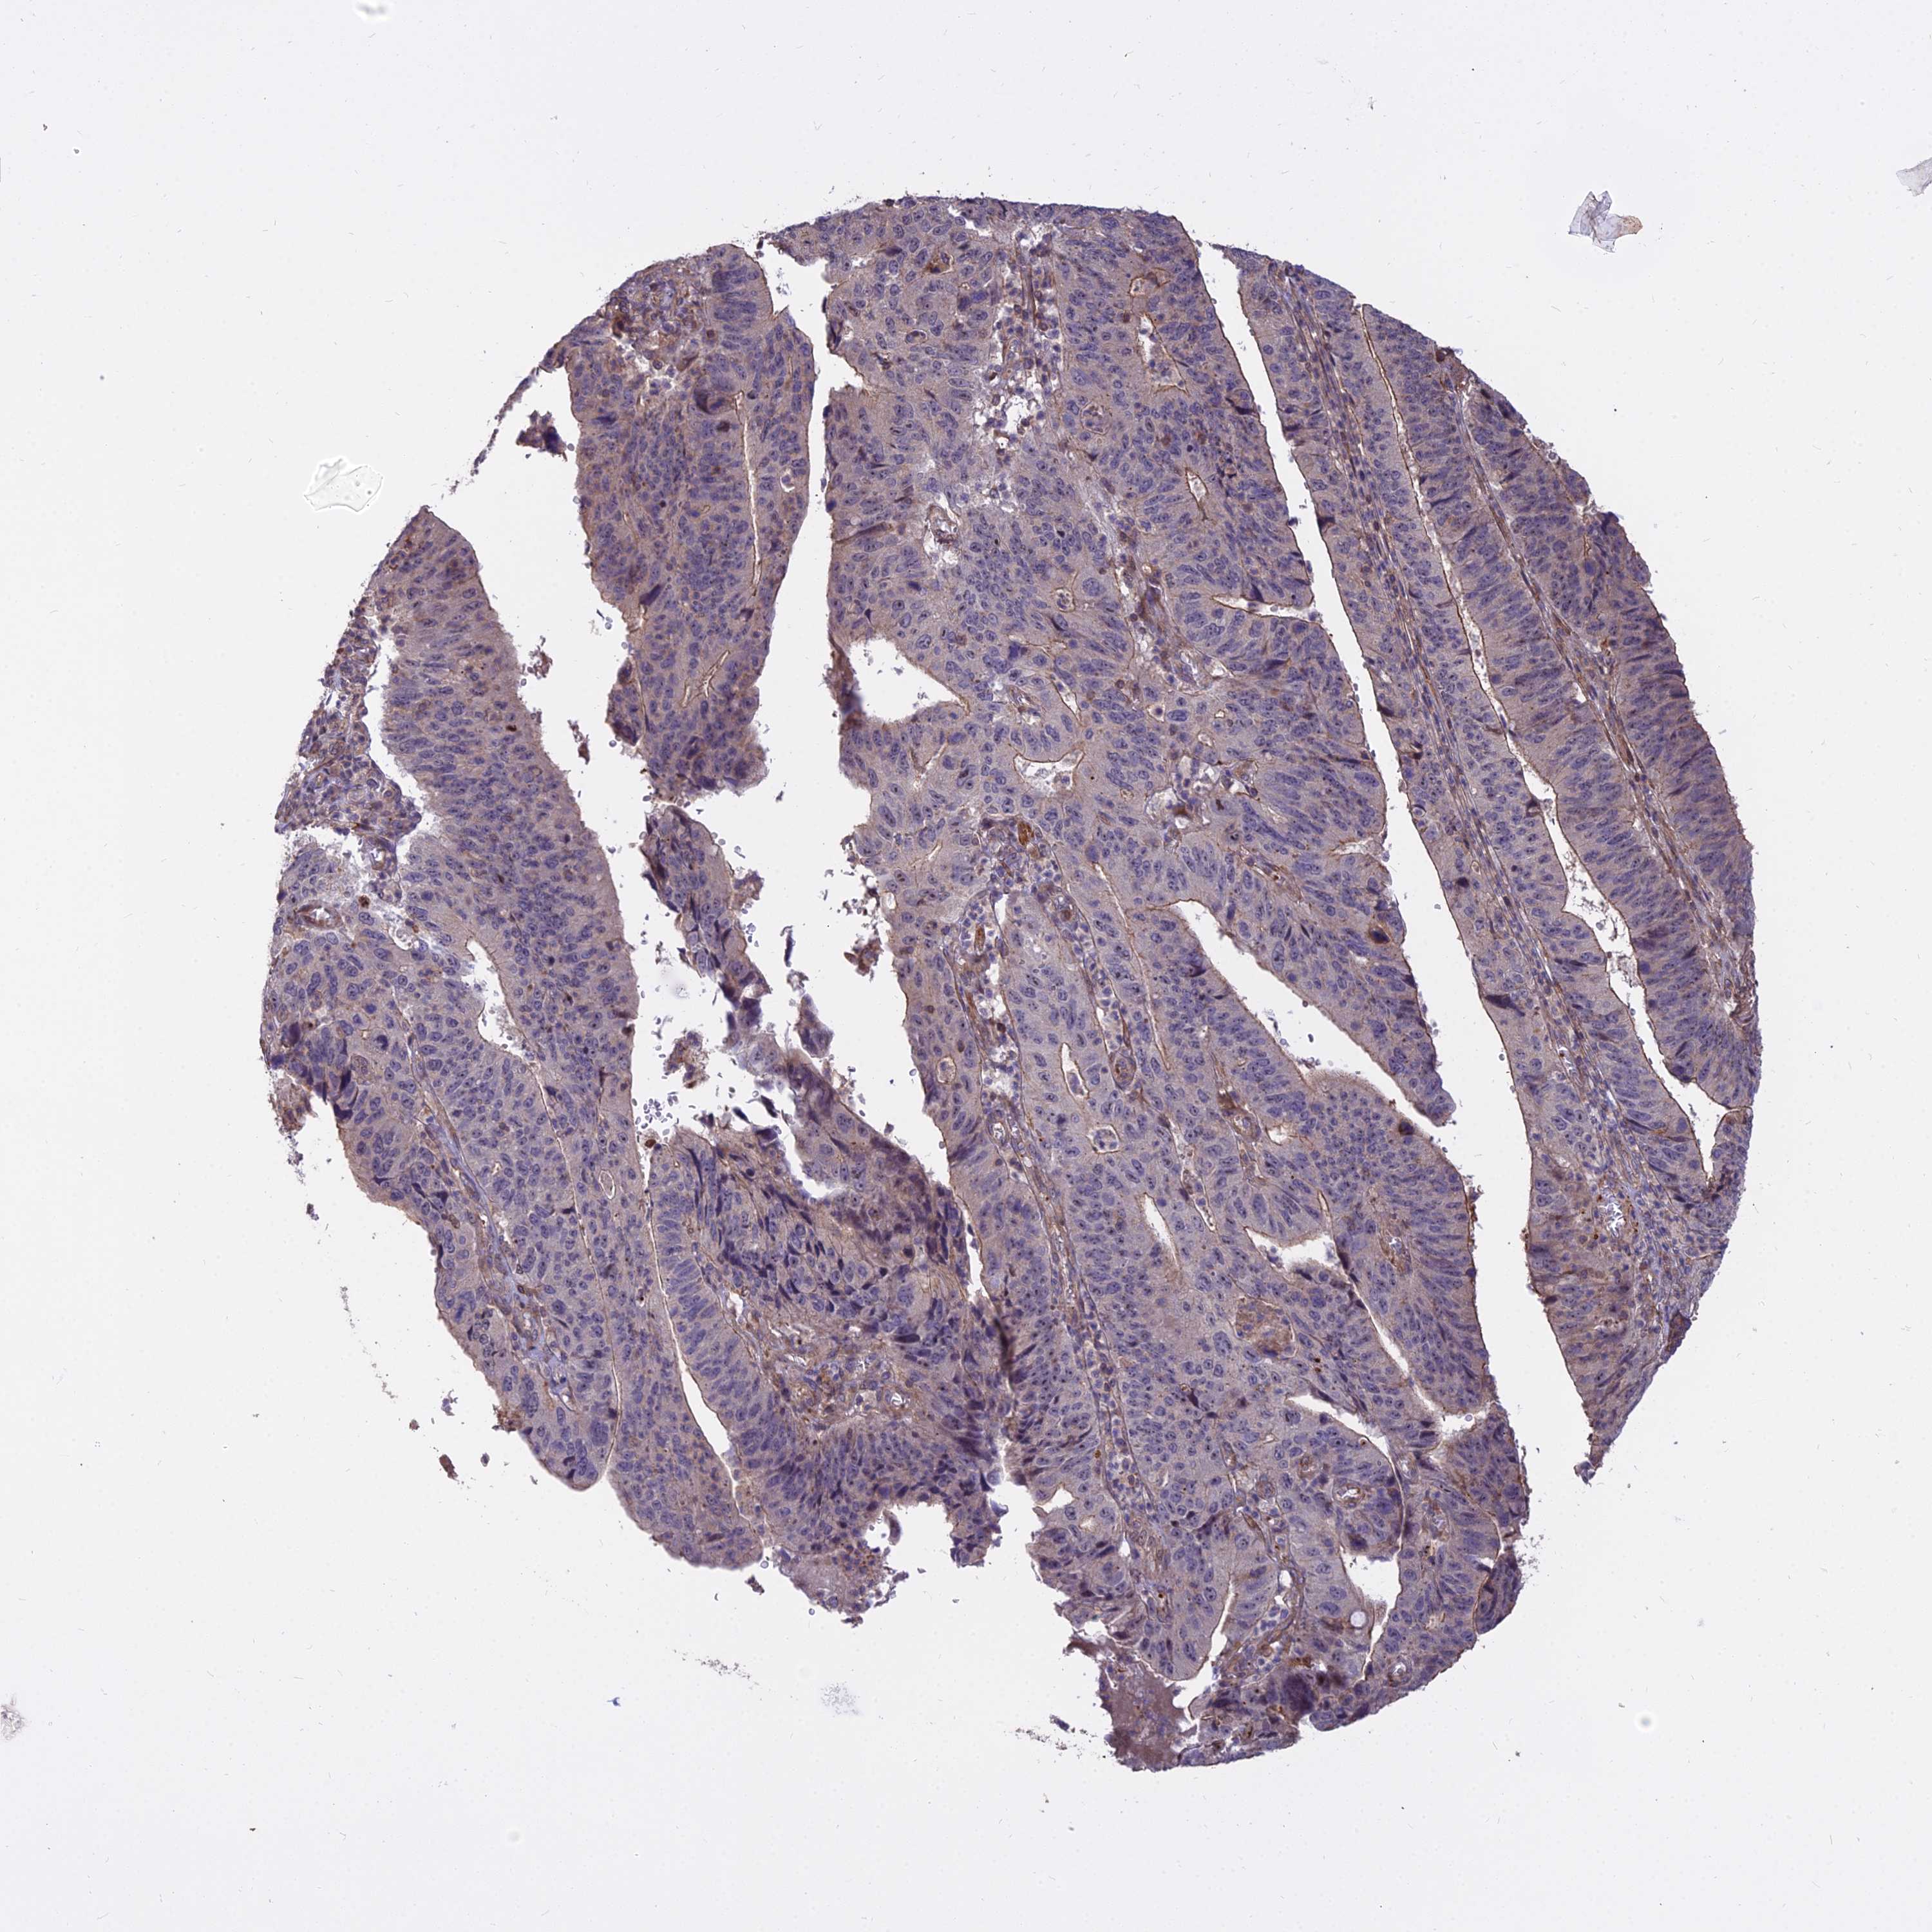

STOMACH CANCER - Protein expressioni

A mouse-over function shows sample information and annotation data. Click on an image to view it in a full screen mode. Samples can be filtered based on level of antibody staining by selecting one or several of the following categories: high, medium, low and not detected. The assay and annotation is described here.

Note that samples used for immunohistochemistry by the Human Protein Atlas do not correspond to samples in the TCGA dataset.

Antibody stainingi

Antibody staining in the annotated cell types in the current human tissue is reported as not detected, low, medium, or high, based on conventional immunohistochemistry profiling in selected tissues. This score is based on the combination of the staining intensity and fraction of stained cells.

Each image is clickable and will lead to virtual microscopy that enables deeper exploration of all samples and also displays staining intensity scores, fraction scores and subcellular localization as well as patient and tissue information for each sample.

Antibody HPA044960

Staining

High

Medium

Low

Not detected

Intensity

Strong

Moderate

Weak

Negative

Quantity

>75%

75%-25%

<25%

None

Location

Nuclear

Cytoplasmic/membranous

Cytoplasmic/membranous,nuclear

Adenocarcinoma, NOS